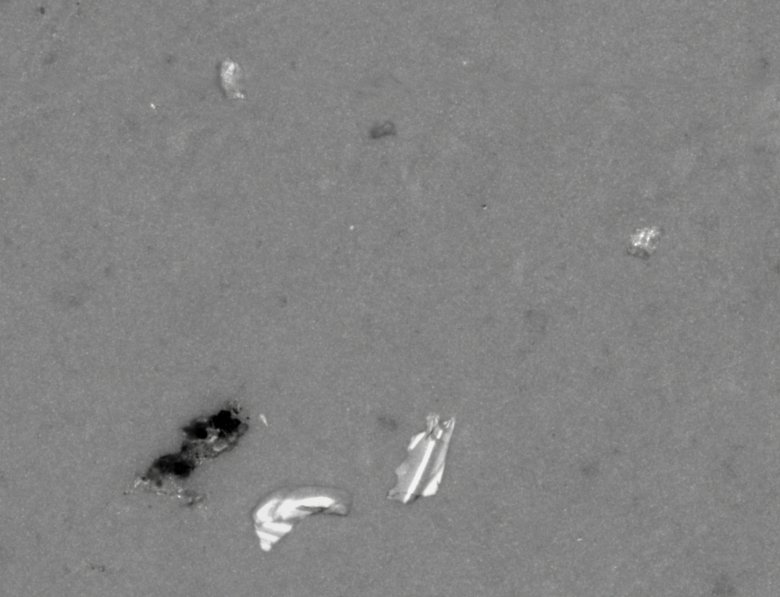

顯微鏡下的顆粒形貌

如上圖,是某在研注射液在顯微計數法不溶性微粒儀下的真實照片,可見其中有金屬顆粒和橡膠顆粒,顆粒粒徑<50μm,為肉眼不可見。所以我們認為的澄清注射液中卻大有乾坤。這些不溶性微粒經過注射器就會進入我們的血管,然后通過血液流動而流經全身,且無法被人體溶解和腎臟排出,從而造成血管壁的聚集和堵塞,造成血栓,是藥三分段,用錯藥錯用藥很容易治病不成而造成二次傷害。